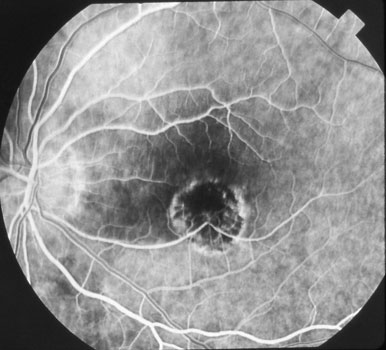

Laser photocoagulation surgery has traditionally been the standard treatment for patients with ocular histoplasmosis and macular neovascularization outside the macular center. When macular neovascularization is beneath the center of the macula, laser not only destroys these abnormal vessels but also permanently damages the overlying retina. Patients are thus left with a dry scar but no central vision. Photodynamic therapy, which became available in 2000, was the first modality that allowed treatment of these central lesions while minimizing retinal damage. The treatment involves injecting Verteporfin (Visudyne) intravenously, followed by painless laser treatment. Direct daylight exposure within the first 48 hours can cause a severe skin burn, so patients need to remain inside for two days following treatment. Photodynamic therapy is painless and is associated with minimal to no side effects.

The goals of treatment are to prevent macular neovascularization from spreading into the macular center (laser photocoagulation), or limit the size of and leakage from the MNV once it reaches the macular center (photodynamic therapy, vascular endothelial growth factor inhibitors).